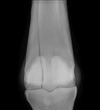

What is the most likely Dx?

D) osteochondrosis